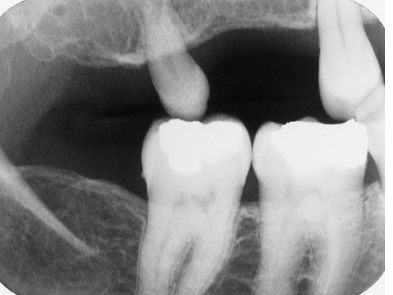

What term(s) best describe(s) the most distal mandibular tooth?

supernumerary

microdont

cute

all of the above